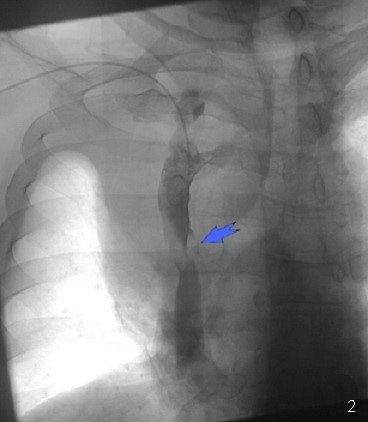

Səbəbin təyini

YBV sindromu təyin edildikdən sonra vacib məsələ səbəbin təyinidir. Əksər hallarda anamnez və KT səbəbi müəyyənləşdirməyə imkan verir (kateter, travma, tromboz, törəmə və s.). Lakin mediastinal törəmə tapıldıqda  onun təbiətini müəyyənləşdirmək üçün biopsiya lazım gələ bilər. Əvvəllər kəskin formalı YBV sindromunda diaqnozu dəqiqləşdirmə müddətində sıxılmanı azaltmaq və vəziyyəti yüngülləşdirmək üçün təcili olaraq radioterapiya aparılırdı. Lakin radioterapiya histologiyanı dəyişdirir. Ona görə də hazırda kəskin durğunluğu azaltmaq üçün venoz stentlərdən istifadə edilir (Şəkil 18).

Şəkil 18. Kavaqrafiya.  YBV-ya stentin qoyulması (1-2)